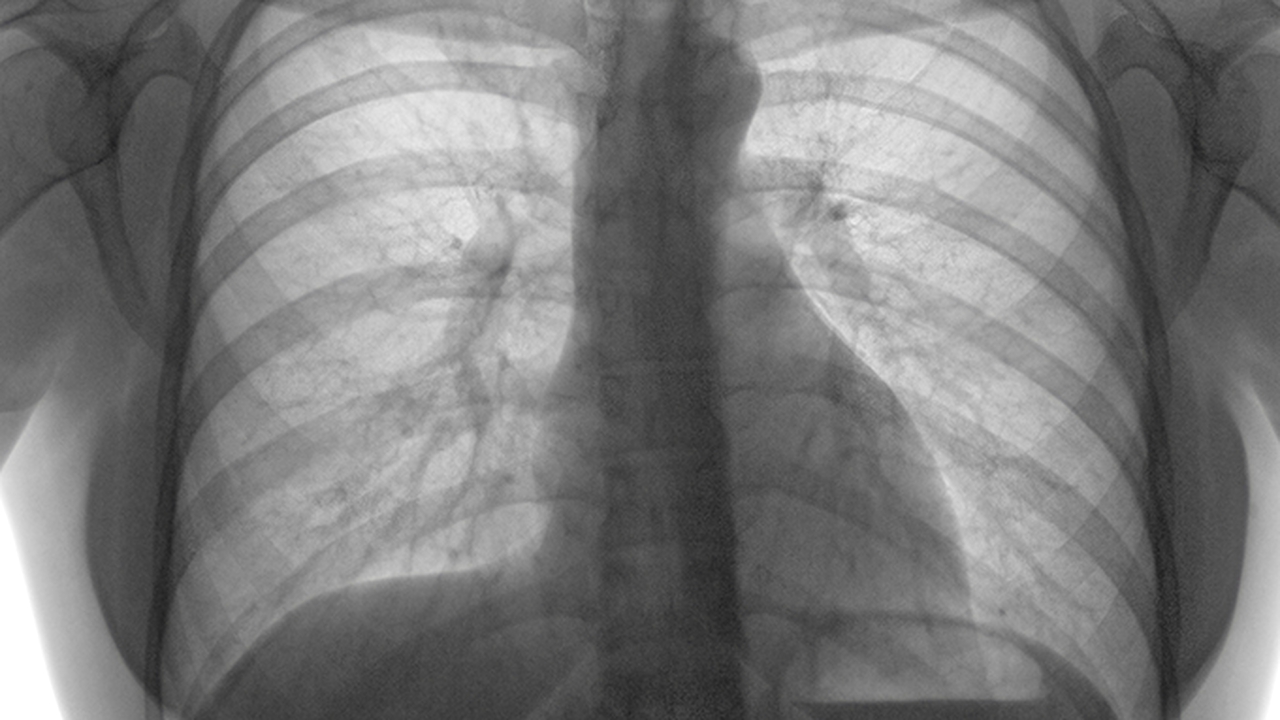

南京鼓楼医院是江苏省内知名的三级甲等综合医院,其呼吸内科在肺结节诊断和治疗方面具有丰富的临床经验。医院配备了的影像学检查设备,如高分辨率CT和PET-CT,能够准确评估肺结节的性质。同时,医院还开展了经皮肺穿刺活检、支气管镜检查和胸腔镜手术等多种诊疗技术,为患者提供个性化的治疗方案。

江苏省人民医院呼吸与危重症医学科是国家临床重点专科,在肺结节诊疗方面具有显著优势。医院拥有多学科协作团队,包括呼吸科、胸外科、影像科和病理科专家,能够为肺结节患者提供全面的评估和治疗方案。医院还开展了肺结节人工智能辅助诊断系统,提高了诊断的准确性和效率。

肺结节的预防与健康管理至关重要。首先,戒烟是预防肺结节的重要措施,吸烟是导致肺部疾病的主要危险因素之一。其次,保持良好的生活习惯,如均衡饮食、适量运动和充足睡眠,有助于增强免疫力,减少肺部疾病的发生。此外,定期体检和肺部CT检查有助于早期发现肺结节,及时进行干预和治疗。对于已经发现肺结节的患者,应定期随访,密切关注结节的变化情况,必要时及时就医。